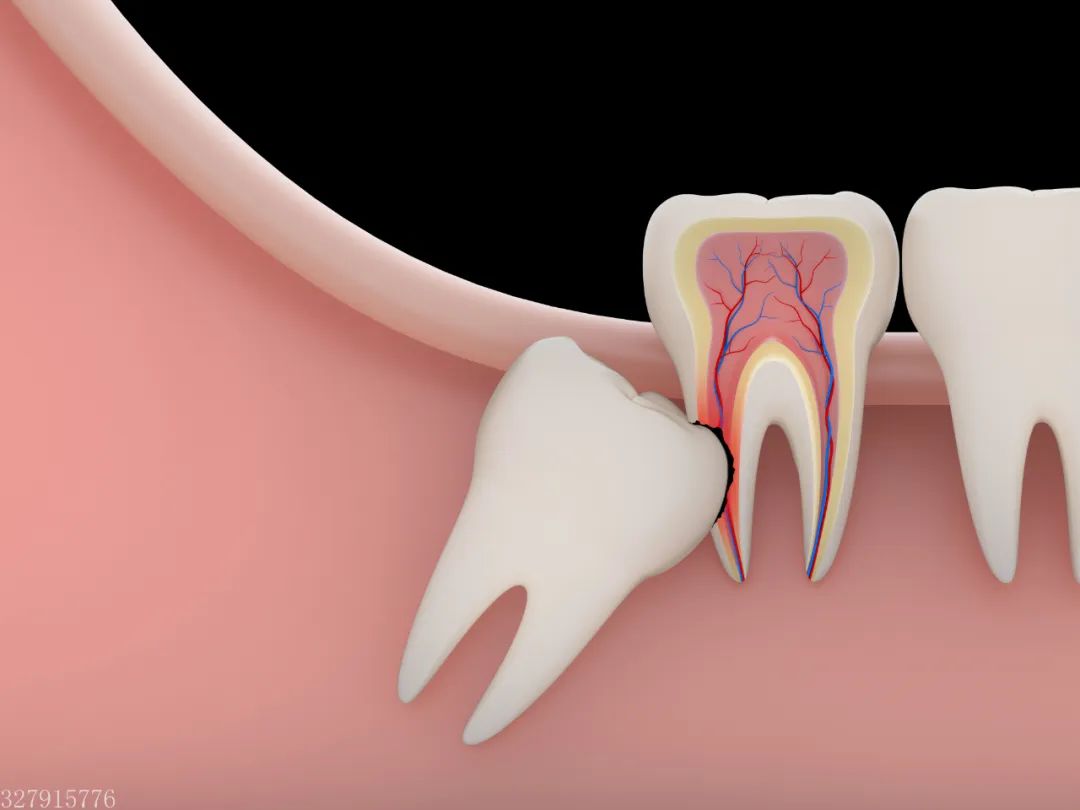

炎症因子、毒素等会顺着血流流经身体各个部位,引起局部红肿、呼吸困难,甚至危及脏腑,造成生命威胁。这是因为,长歪的智齿不容易清洁,食物常常会留在智齿周围,不仅容易导致智齿疼痛,还容易导致智齿前方的磨牙变为蛀牙,从而引起更大范围上的牙痛。

到了那个时候,智齿要拔掉不说,智齿前方的磨牙也会出现不可挽救的龋坏,只能一起拔掉。而且,智齿拔掉之后不需要镶牙,最多花个几百一千块。但如果前方的磨牙被拔掉,就只好通过种植牙进行修复。